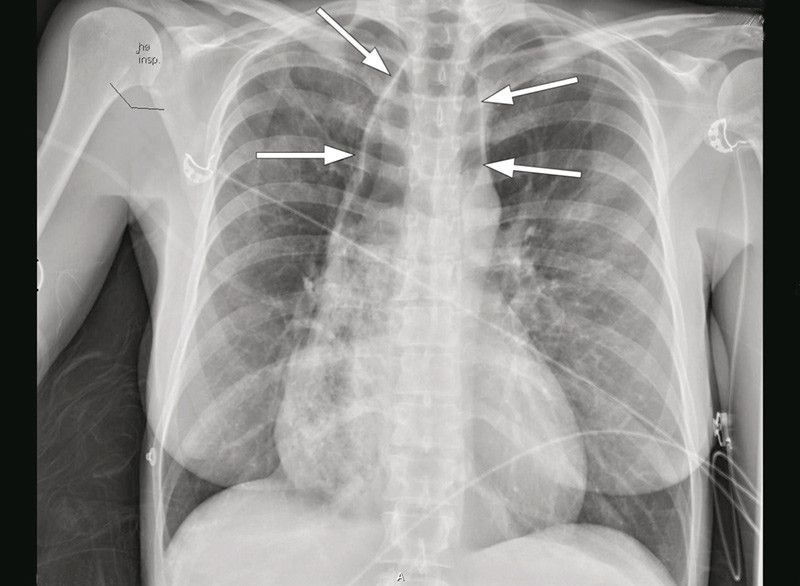

Vi mistenkte nå oesophagusakalasi. Luften som var projisert over mediastinum ved innkomst (fig 1), var sannsynligvis luft i en dilatert oesophaugus og ikke uttrykk for pneumomediastinum, som først antatt. MR oesophagus viste slynget og dilatert (> 6 cm proksimalt) oesophagus med innhold, stenose ved overgangen til ventrikkel og små bilaterale lungefortetninger. Det var bildemessig ikke mistanke om stenoserende malignitet (fig 2).